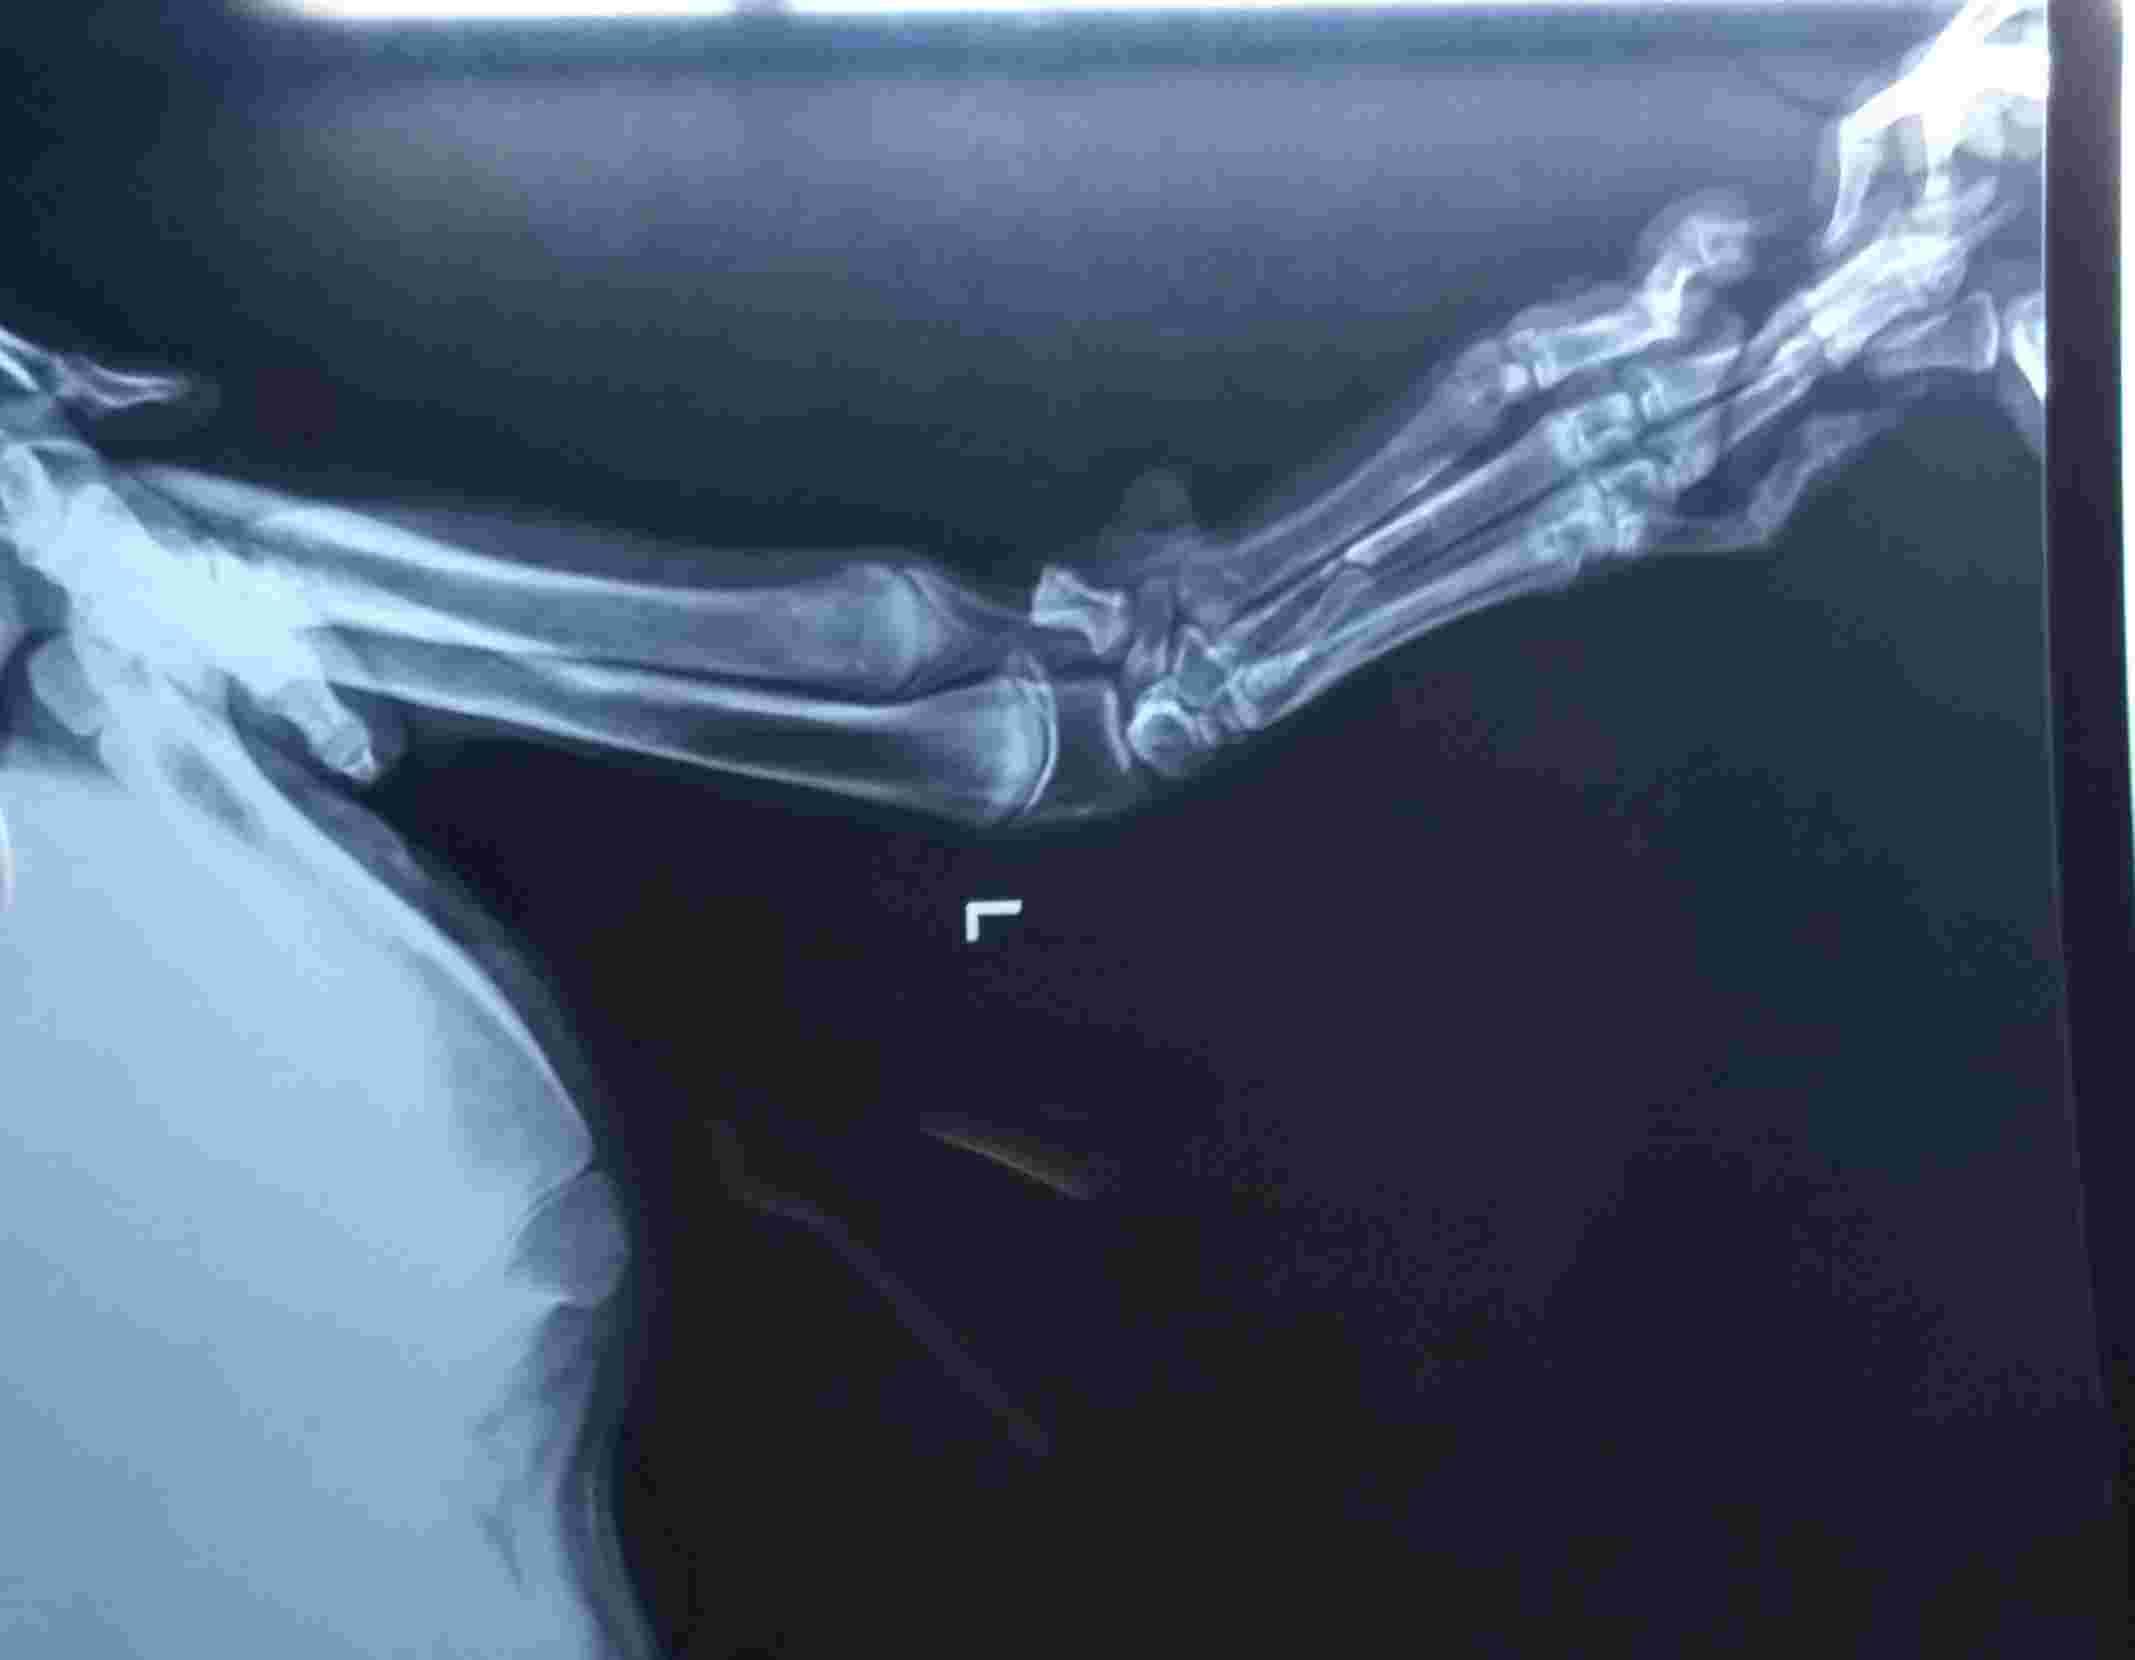

What causes carpal valgas deformity ? Is smooth surface like glossy tiles walking on them or running is the cause of this carpal valgas? If not mention the cause also at his this age of almost 3 yrs if I going to wrap splints on his legs then will this valgas will going to correct or it will going to be like this only? Also I am attaching xrays of his bith front legs kindly see the attachment to confirm me whether valgas is showing in the xrays or not

This can be from his genetics or breeding or can develop after an injury. Splinting the carpus will help prevent the condition from worsening when used during exercise but will not correct the problem. Yes the X-rays show a valgus deformity. This is a dog I would not breed since you don’t want to take the chance of this being passed on to the puppies. I recommend a consult with a board certified orthopedic surgeon to see if there is corrective surgery or any rehabilitation treatment they recommend. Thanks for using Petco Pet Education Center, formerly Petcoach to help you care for Danny.